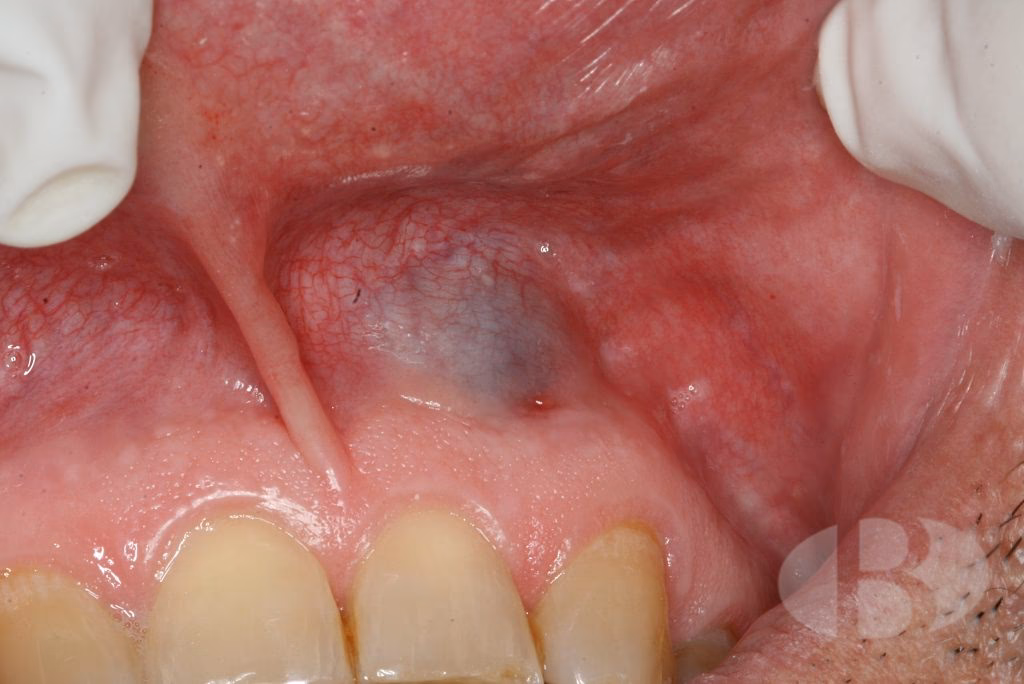

El aspecto clínico de los hemangiomas es sumamente variable, lo que puede dificultar su diagnóstico visual. Pueden presentarse como pequeñas lesiones superficiales, apenas perceptibles, o como extensas formaciones que llegan a provocar deformaciones significativas en las estructuras involucradas de la cavidad bucal o la cara. La coloración de estas lesiones depende en gran medida de su profundidad y del tamaño de los espacios vasculares que las componen:

- Lesiones superficiales: Suelen tener un color rojo purpúreo o rojo violáceo. Esto se debe a que los vasos sanguíneos son grandes, numerosos y están situados cerca de la superficie.

- Lesiones profundas: Pueden variar de un color más tenue, desde rosado hasta rojizo. Si los espacios vasculares son pequeños, profundos y formados por una mezcla de conductos arteriales y venosos, el color puede ser violeta o azulado.

Una característica distintiva de muchos hemangiomas es que palidecen cuando se ejerce presión sobre ellos. Esto ocurre porque la sangre es forzada a salir de los espacios vasculares, para luego volver a llenarse al liberar la presión. Esta maniobra, conocida como diafanoscopia, es una herramienta diagnóstica útil en el examen clínico.

Hemangioma Cavernoso

Los hemangiomas cavernosos se diferencian de los capilares por la presencia de conductos vasculares más amplios, de mayor calibre. En lesiones pequeñas, pueden observarse uno o dos conductos vasculares que forman la totalidad de la lesión. Macroscópicamente, se presentan como una masa esponjosa de color rojo azulado. Histológicamente, no están encapsulados y están formados por grandes canales vasculares irregulares, llenos parcial o completamente de sangre. Estos canales están separados por una cantidad variable de tejido conjuntivo.